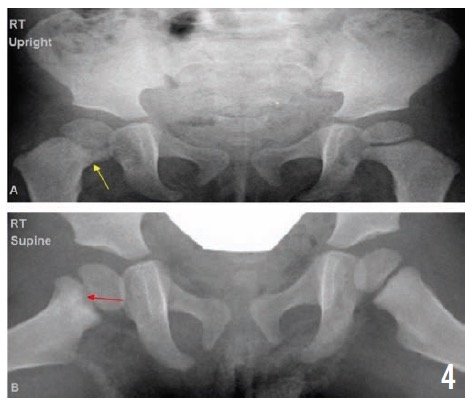

Radiographs of the pelvis at 2, 4, and 10 months (Figures 3, 4, and 5, respectively) showed healing osteomyelitis of the proximal right femur and changes that were concerning for early physeal closure at the right hip joint. Continued radiographic follow-up was suggested at that time.